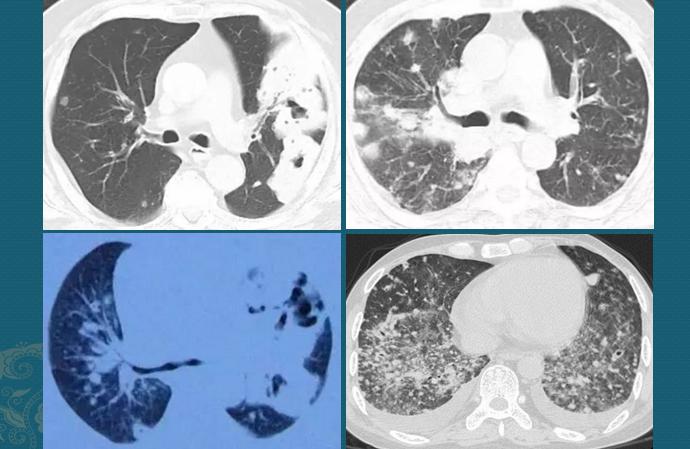

下面4位病人,都是病原学确诊的诺卡菌肺炎,病情进展后几乎都会形成空洞:

部分病例来自网络

诺卡菌空洞有一个显著特点是:几乎看不到液平面。就是说,空洞里常常没有液态的脓液,是崩解的坏死肺组织、含有菌丝的细菌、炎症细胞、少许液化坏死组织等共同组成的碎渣状物,甚至有种土腥气(泥土味的诺卡菌混合坏死组织),是个重要提示。